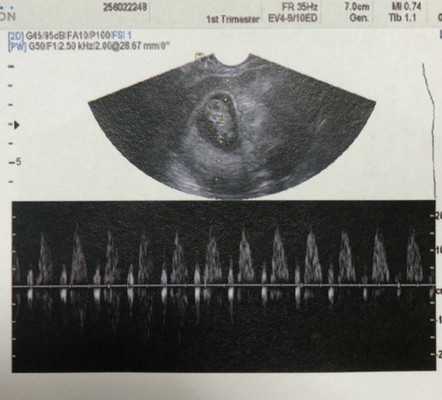

ขอแชร์เรื่องราววันนี้ค่ะ วันนี้ 31/10/2020 ตั้งครรภ์ ครบ 9 weeks พอดี ค่ะ เหตุเกิดจากเสียบปลั้กไฟ ที่ไฟรั่ว แล้วโดนไฟช๊อต รีบดึงมือออก มือชา ค่ะ กังวลมาก บอกสามี สามีบอกไม่เป็นไรหรอก เราก็กลัวลูกในครรภ์จะเป็นอะไรไป ขอให้พาไปหาหมอ อัลต้าซาวน์เลยได้ไหม เขาก็ดูหงุดหงิด เราร้องไห้เลยค่ะ แต่สุดท้ายเขาก็พาไปหาหมอค่ะ ที่ รพ ใกล้บ้าน ไฟช้อต 12.30 น ไปหาหมอ 14.00 ค่ะ ผลอัลต้าซาวน์ ลูกหัวใจยังเต้นปรกติดีค่ะ โล่งค่ะ จะระวังตัวให้มากกว่านี้ คุณหมอบอกว่า ไฟช้อต ถ้าลูกจะเป็นอะไร แม่ต้องโดนไฟช้อตขนาดหัวใจเกือบหยุดเต้นค่ะ เป็นห่วงตัวแม่มากกว่าค่ะ